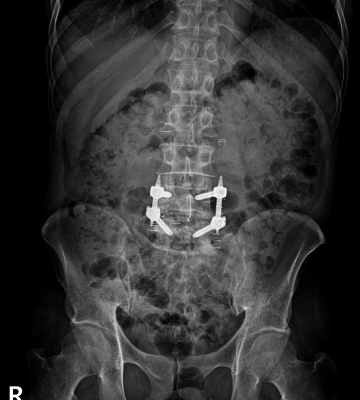

척추분리증 수술 전·후

2023.01.17

ㆍ환자 동의를 받은 자료이며, 이미지 사진은 실물과 다를 수 있습니다.

ㆍ모든 자료는 새움병원 자료입니다.